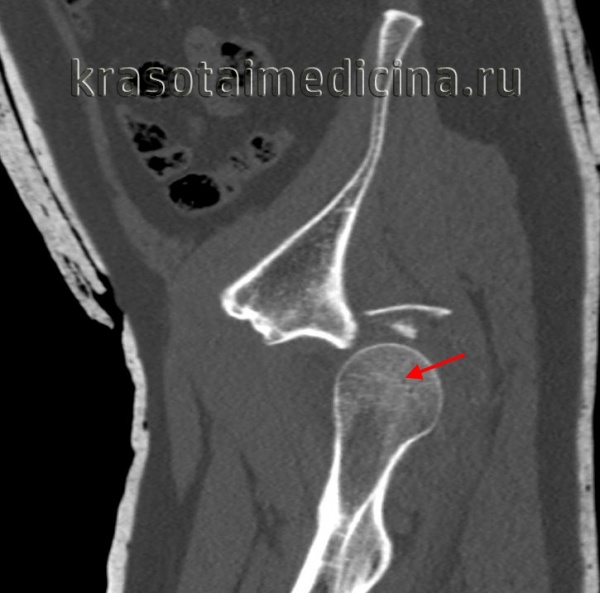

(Слева) КТ в передне-задней проекции, объемная 3D реконструкция: определяется задний вывих головки бедренной кости. КТ выполняется перед закрытой репозицией только если она оказалась неудачной. КТ позволяет оценить положение смещенных осколков, препятствующих репозиции.

3. КТ при вывихе бедра:

• Смещение головки бедренной кости

• Сопутствующие состояния:

о Переломы стенки вертлужной впадины четко определяются

о Трещина или вколоченный перелом головки бедренной кости:

- Аналог перелома Хилла-Сакса при суставно-плечевом вывихе

о Внутрисуставные костные осколки:

- Могут помешать закрытой репозиции

(Слева) КТ, аксиальный срез: в данном вывихе, репозиция которого возможна только под общей анестезией, визуализируется головка бедренной кости, вколоченная в заднюю губу вертлужной впадины.